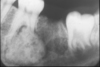

Osteosarcoma

Freq in long bones: proximal tibia/distal femur, in pubescent boys. Gnathic osteosarcs = older age, average 35. X-ray hallmarks of osteosarcoma: asymm widening of PDL space; bone formation in soft tissue; bone formation above the alveolar crest. Spiking root resorption; irregular, ill-defined borders; may be RL to Mixed to RO; “Sun-burst” only in 25% of jaw osteosarcs. Radical resection is only effective tx.